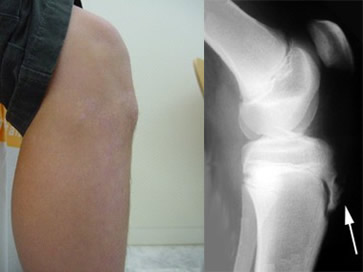

La enfermedad de Osgood-Schlatter se caracteriza por un dolor que aparece al realizar actividades físicas (caminar, correr, saltar…), justo por debajo de la rodilla, en la parte anterior. Se acompaña de inflamación local y dolor importante al tocar esa zona.

Es conveniente que un traumatólogo valore si el dolor de la rodilla corresponde a este proceso porque existen muchas otras causas de dolor en la rodilla. Mediante ecografía puede realizarse un diagnóstico rápido en nuestra consulta.

Si el traumatólogo lo considera oportuno le pedirá una radiografía para estudiar el estado del cartílago de crecimiento.